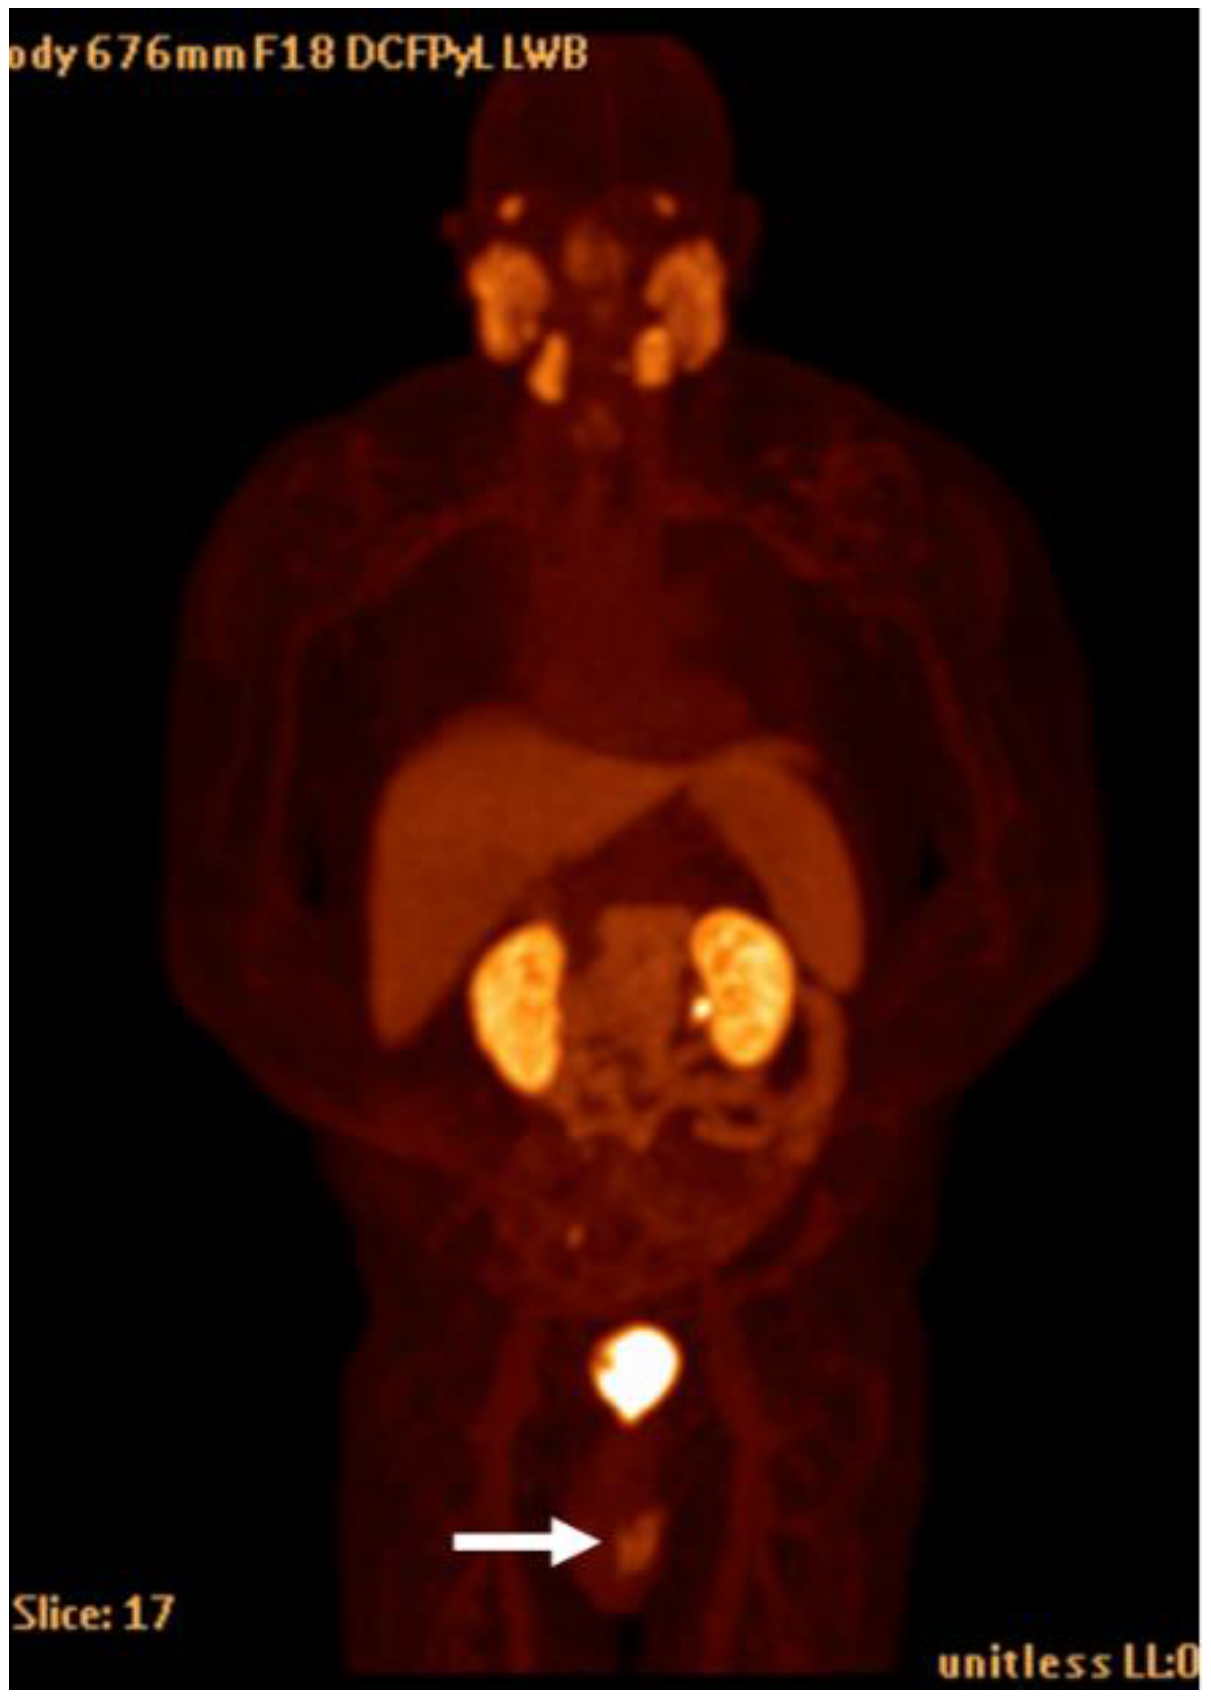

Detection of Loco-Regional Disease and Distant Metastases

1.9.3. Pearls and Pitfalls